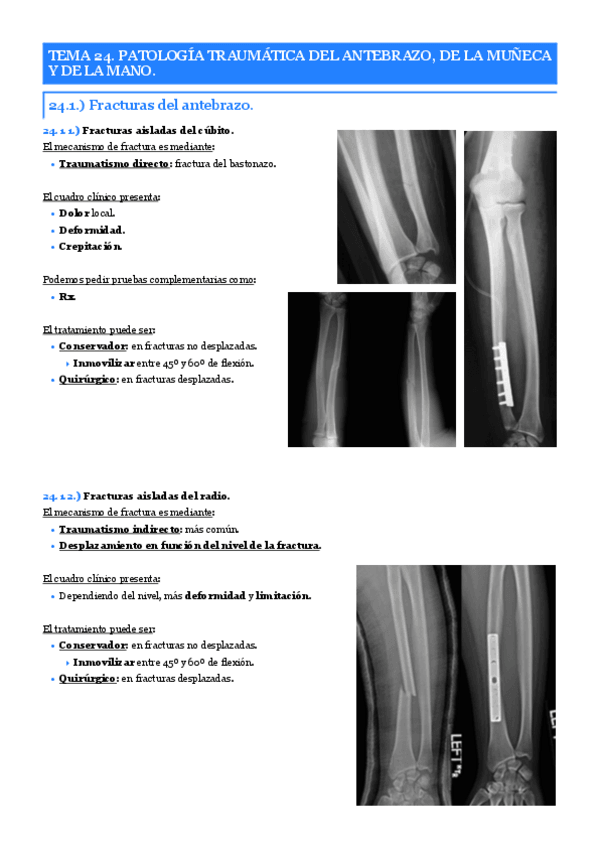

He publicado nuevos apuntes de 2º Patologia Médica y Farmacología I: Tema-24.-Patologia-traumatica-del-antebrazo-de-la-muneca-y-de-la-mano..pdf